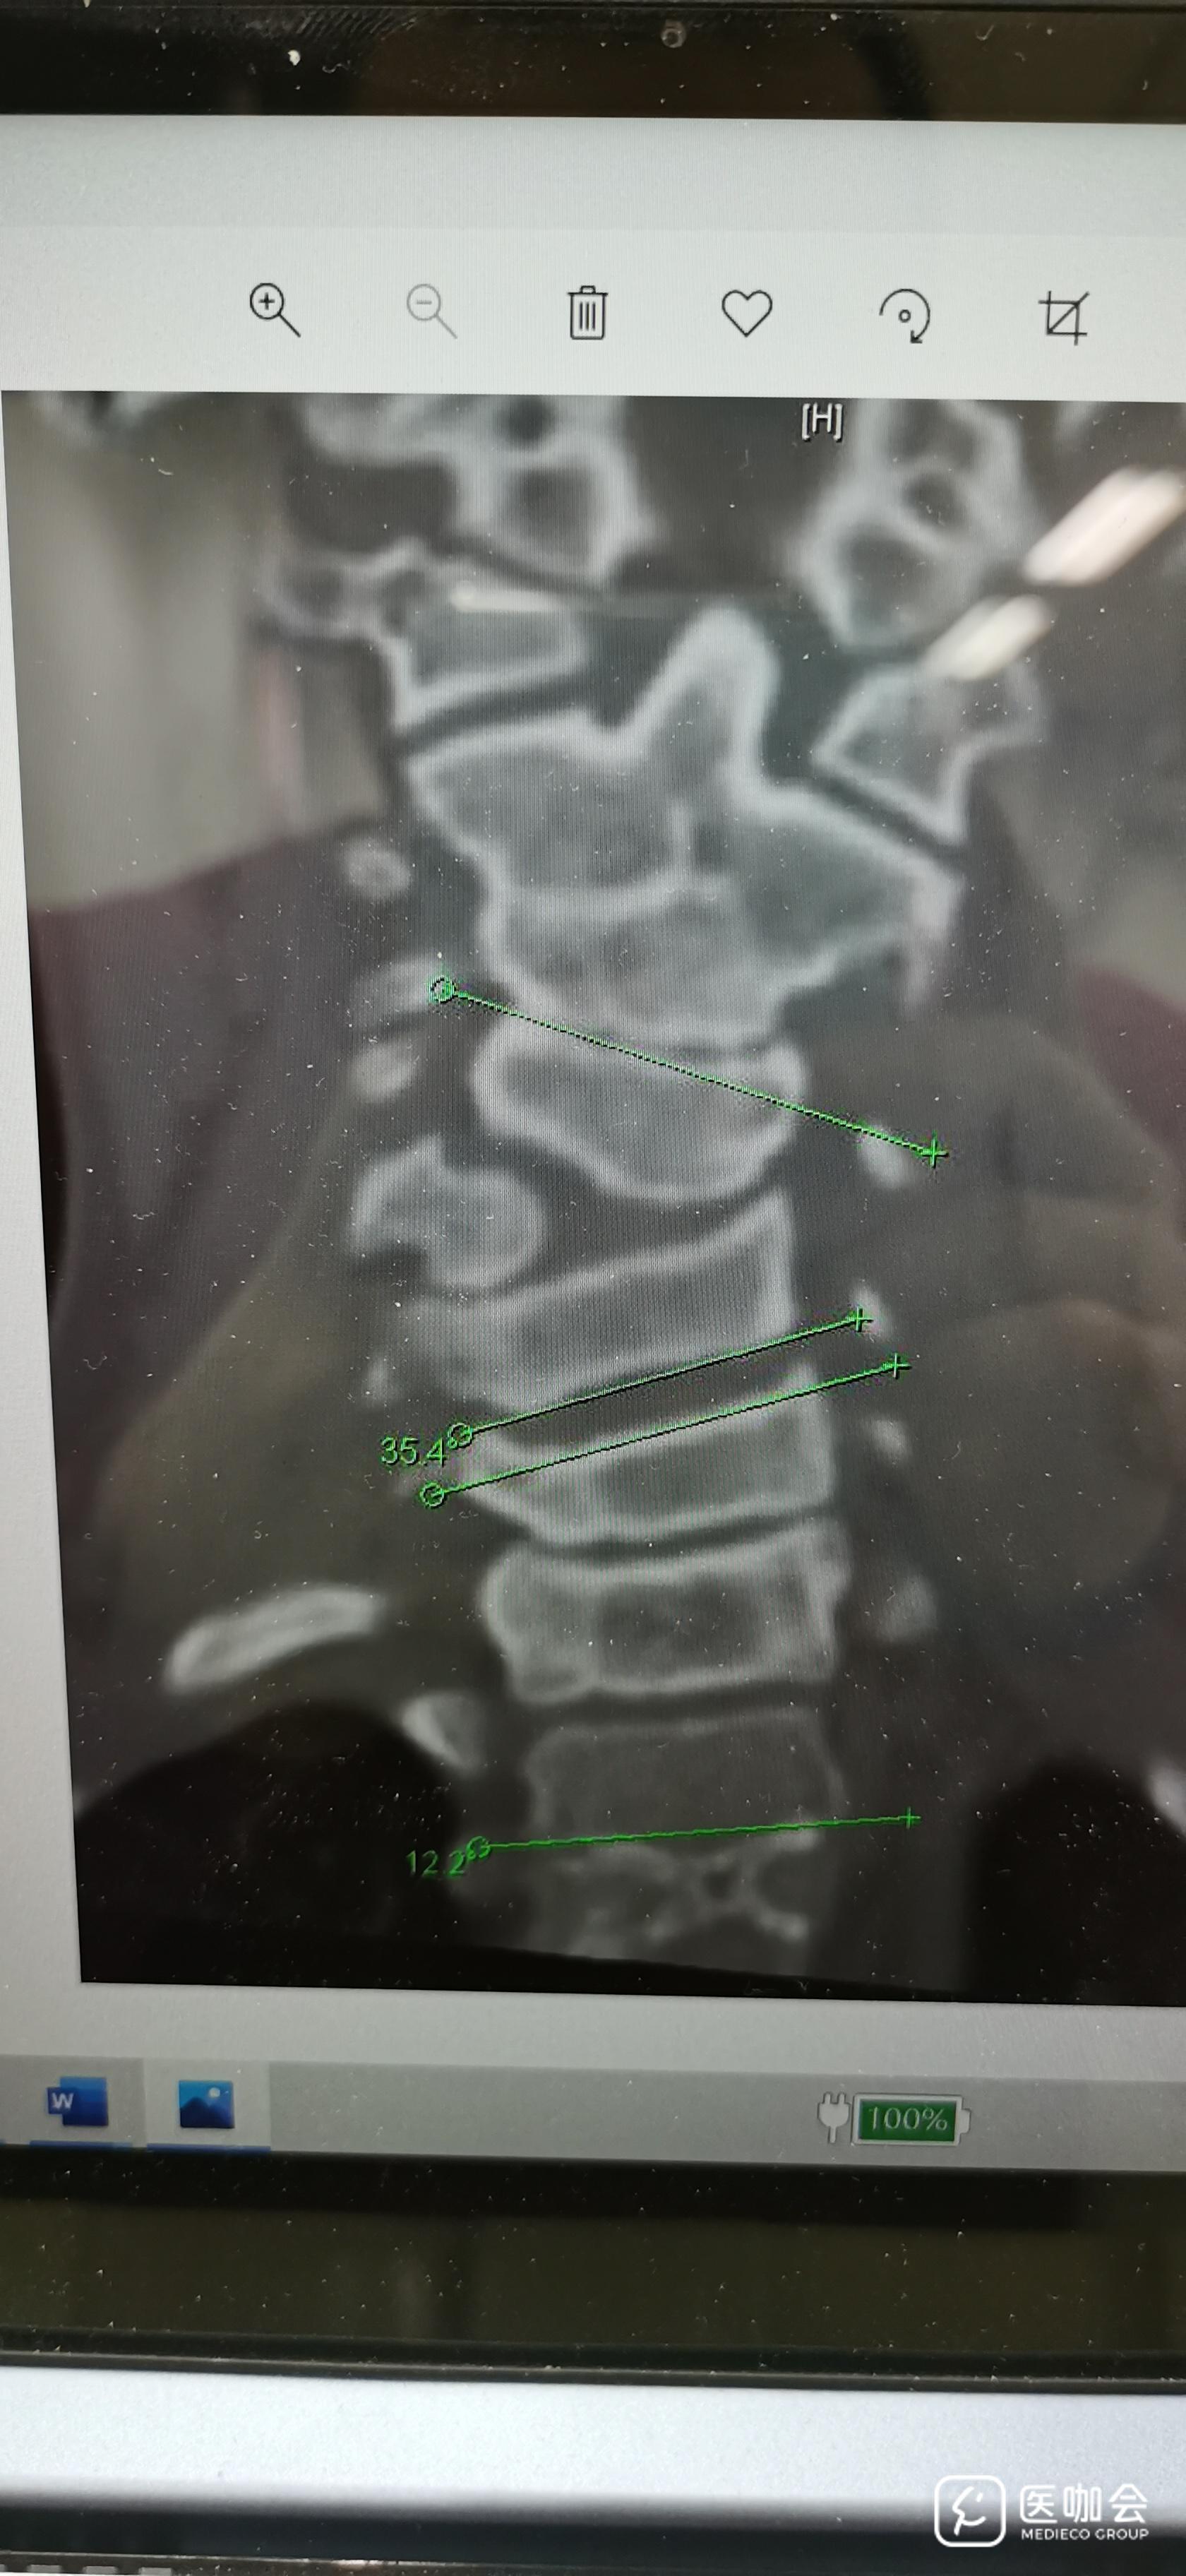

例:如图,ct冠状位,可见侧弯角度35.4度。

研究50例颈椎侧方弯曲畸形患者,从影像片子上测量出每个患者颈椎弯曲角度依次为a1,a2...a50。(备注:从颈椎CT冠状位片子可见,正常人无颈椎侧弯,即角度为0度。数据均大于0度,为连续变量)